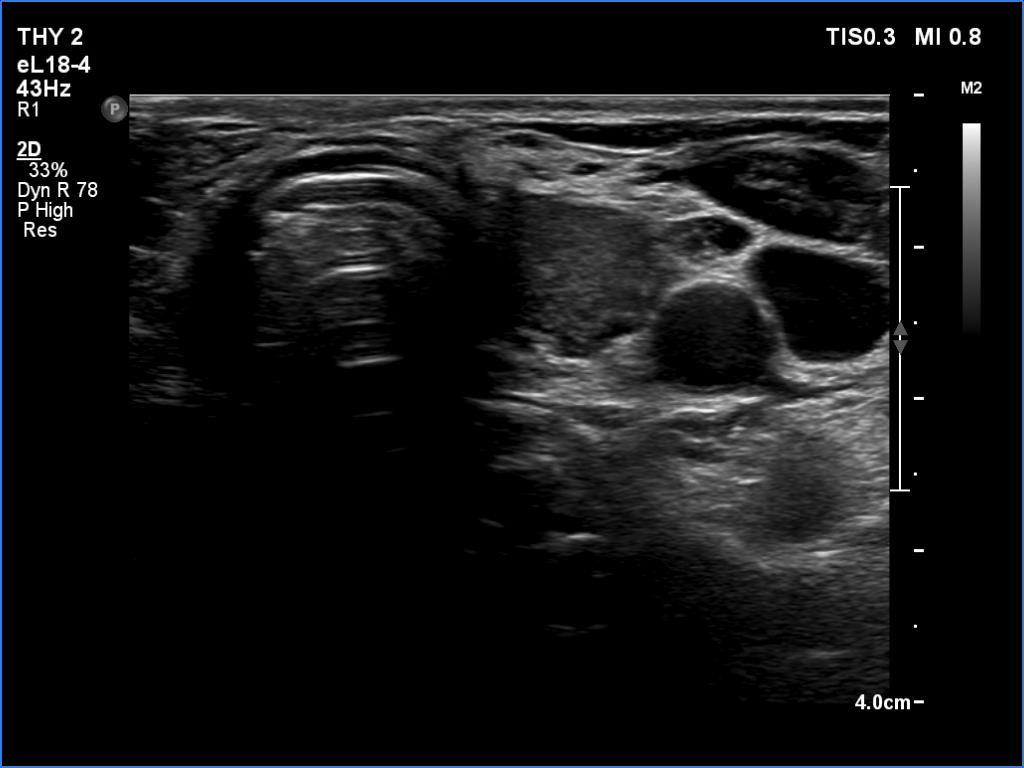

Second examination (second row of images):

Clinical data: The patient came to a routine follow-up.

Palpation: no abnormality.

Laboratory tests: TSH 3.84 mIU/L on daily 75 microgram levothyroxine.

Ultrasonography. The presentation of the thyroid was essentially the same. The mass in question became smaller. This was avascular and proved to be hard on elastography.